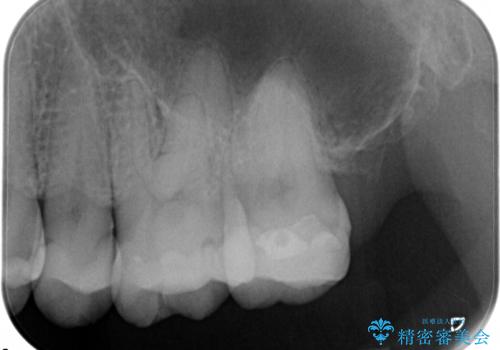

虫歯の治療(セラミックインレー)

- 定期検診にて虫歯が見つかり、セラミックインレーにて修復しております。

e-max プレスインレーにて修復治療を行っているため適合性及び審美性の高い治療を行うことができます